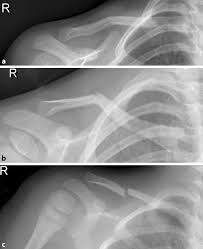

Eine erste Röntgenkontrolle sollte nach ca. Die meisten Brüche sind nach 12 Wochen stabil ausgeheilt. Selten wachsen die Bruchenden nach einer konservativen oder operativen Behandlung nicht richtig zusammen Pseudarthrose.

Die Reposition der Fraktur dh. Eine teilweise Metallentfernung am Sprunggelenk findet etwa sechs Wochen nach der Haupt-OP statt. Dauer der Therapie einer Schlüsselbeinfraktur Die Gesamtdauer der Therapie beträgt in der Regel 6-8 Wochen bei problemlosen Verlauf.

Schlusselbeinbruch Symptome Behandlung Heilungsdauer Op Und Rucksackverband Onmeda De